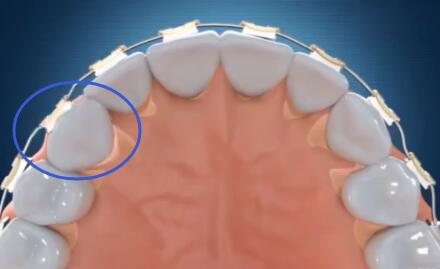

虎牙埋伏牙牽引示意圖

虎牙牽引完成